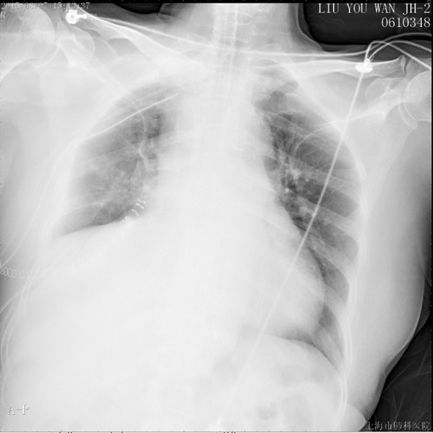

现病史:患者入院前体检发现右下肺占位28天,院外右下肺穿刺活检提示孤立性纤维性肿瘤,转入本院全麻下行心包内右肺中下叶切除和右胸腔肿块切除术,手术时间2.5h,术中失血100ml,无输血,术后病理显示梭形细胞肉瘤,倾向恶性孤立性纤维瘤,术后安返胸外科ICU,术后第一日胸引量350ml,无殊转回普通病房。次日凌晨患者下床如厕后突发胸闷气促,脸色苍白,四肢湿冷,无晕厥。面罩吸氧后仍诉胸闷气促无法缓解。心电监护:SPO2 70%,HR 100-120bpm,BP 110/80mmHg。实验室检查:血气分析:pH 7.16↓, PaCO2 56.5mmHg, PaO2 43mmHg↓, SpO2 62.2%↓。

描述:溶栓2h后,胸引量:400ml

描述:溶栓18h后,胸引量:1700ml

描述:溶栓2d后,胸引量:150ml

描述:溶栓3d后,胸引量:100ml

初步治疗:吸氧;经鼻气管插管,机械通气;低分子肝素6000IU皮下注射;患者神志清,自诉症状未缓解,术后第二日予以转入ICU。转入ICU后予机械通气,Vt 480ml,FiO2 100%,HR 128bpm,SPO2和血压进行性降落,需血管活*药性**维持。

此时患者由中高危逐渐转为高危,则予以个体化剂量溶栓治疗:阿替普酶(爱通立)10mg 2min静推,20mg 2h静脉泵入。溶栓2小时后,患者血氧饱和度明显上升,生命体征趋于平稳。后续抗凝维持方案:克赛6000 IU 皮下注射 Q12H。

溶栓18h后,胸引量明显增多,同时提醒胸腔内大量血肿,因此于术后第五日,予以全麻下行VATS剖胸止血术,手术时间1.5h,术中失血600ml,输血球2单位,术后带气管插管入ICU。止血术后第一日胸引量450ml,复查血气正常,予以拔除气管插管,SPO2 96%,HR 81bpm,BP 135/88mmHg。